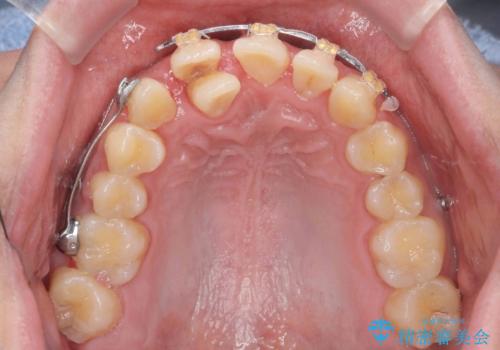

正中過剰埋伏歯で生じた前歯の審美障害 矯正治療での改善

- 前歯の見た目に悩まれて来院されました。

当初他院では、抜歯を行いセラミックブリッジを提案されていましたが、他の方法はないかと総合歯科治療を行う当院へと相談来院されました。

「時間がかかっても良いので、できれば歯を抜かずに矯正治療で治したい。」という強い希望があったので、矯正治療で歯並び・審美性の改善を計画します。